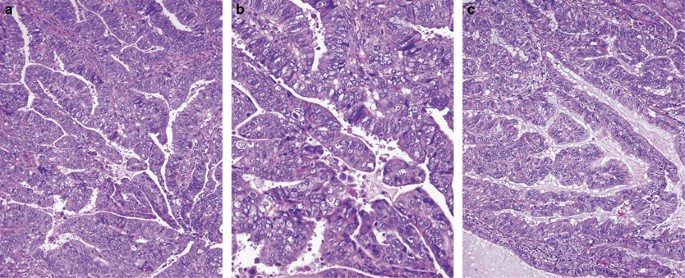

Papillary ECa of intermediate grade (Grade II)

This variant is not recognized in the current WHO classification;2 however, its existence has been acknowledged by some investigators.7, 8 It is characterized by papillary structures, with or without fibrovascular cores, lined by cells with moderate cytologic atypia (ie, nuclear pleomorphism and loss of nuclear polarity). The surface of the papillae is either smooth or slightly irregular (the latter appearance being one of the reasons for which it can be mistaken with serous carcinoma); in addition, mucinous metaplasia is usually noted (Figure 5a–c). In our experience, this pattern tends to be associated with the MELF (microcystic, elongated, and fragmented) pattern of myometrial invasion,8 which is characterized by angulated and/or fragmented glands typically with at least partial attenuation of the epithelial lining and often associated with a fibromyxoid response and aggregates of acute inflammatory cells (Figure 6a–b). In some cases, only single and small cell clusters with abundant eosinophilic or vacuolated cytoplasm resembling histiocytes may be seen within the fibromyxoid stroma or areas of inflammation and can potentially be overlooked. The biological significance of the MELF pattern of invasion is still a matter of debate. One of the earliest studies found an association between this pattern and lymphovascular invasion but overall reported a more favorable patient outcome when present.9 Another study confirmed that the MELF pattern of invasion was not an independent predictor of lymph node metastases.10 However, other investigators have found an association between this pattern, lymphovascular invasion, as well as lymph node metastases.11, 12, 13, 14

In our experience, papillary ECa of intermediate grade, with or without MELF pattern, tends to be associated with vascular/lymphatic invasion and lymph node metastasis. Other investigators have indicated that these tumors appear to have a behavior intermediate between serous carcinoma and ECa villoglandular variant.7 Despite controversy, efforts should be made to identify the MELF pattern of invasion, as it is commonly associated with a deceptive pattern of vascular/lymphatic invasion,11, 12, 15, 16, 17 which is characterized by single and clusters of cells that have a histiocytoid-like morphology. The same cells may be easily overlooked in the subcapsular sinuses of regional lymph nodes (Figure 6c and d). Immunohistochemical studies may be needed to confirm the epithelial nature of these bland cell clusters.16, 17